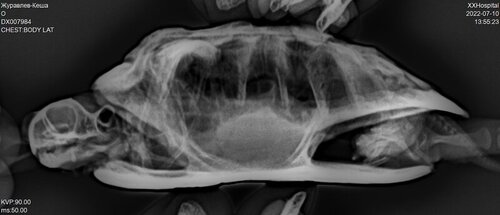

DX007984_1.JPG

DX007984_2.JPG

DX007984_3.JPG

Исправили температурный режим, УФ лампу заказали скоро должна прийти. В телеграмканале не отвечают что делать дальше. Написали про газы в целоме, что делать с ними?